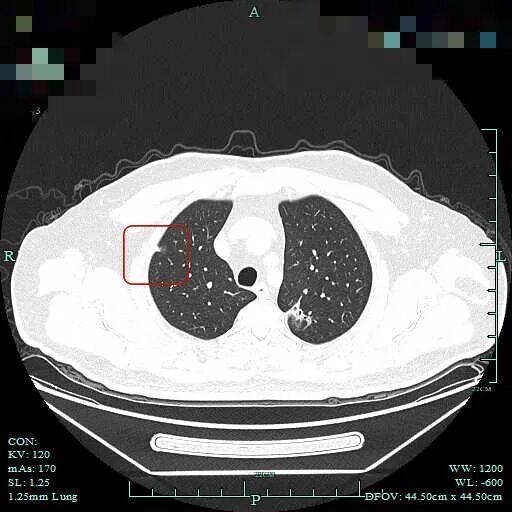

再看2025年10月时该市级中医院的影像:

病灶到了2025年10月范围略有扩大,但不太厉害,不过密度明显增加,表面不平,整体轮廓与瘤肺边界清楚,灶内有条状密度增高,靠右侧向叶间裂处延伸,已经搭上胸膜了。这基本上就是浸润性癌的了!